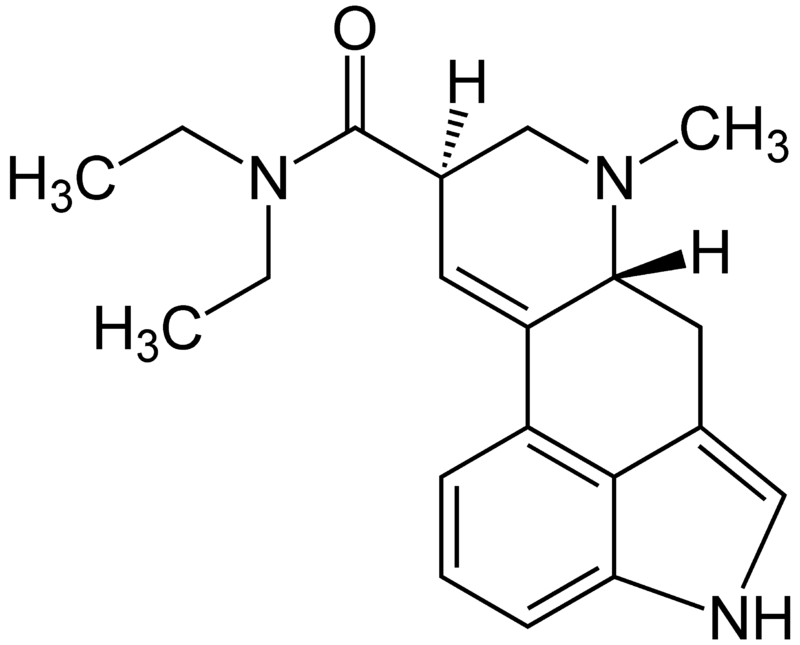

Silicon Valley, cuna de la innovación tecnológica, está experimentando una transformación silenciosa pero profunda: la integración de los psicodélicos en la cultura laboral. Lo que hace años se consideraba marginal o subversivo, hoy se ha convertido en una herramienta legítima para potenciar la creatividad, combatir el agotamiento y redefinir el bienestar en la meca tecnológica. De la marginalidad a la integración terapéutica La llamada integración psicodélica, guiada por terapeutas especializados, es ahora una práctica común entre ingenieros, emprendedores y ejecutivos del sector tecnológico.